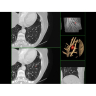

• Широкая область применения: от неврологии до кардиологии и онкологии.

Неврологические исследования

• Выявление инсультов, опухолей головного мозга и травматических повреждений.

• Диагностика заболеваний позвоночника и межпозвоночных грыж.

Онкология

• Раннее выявление новообразований и контроль эффективности лечения.

• Планирование лучевой терапии с высокой точностью.